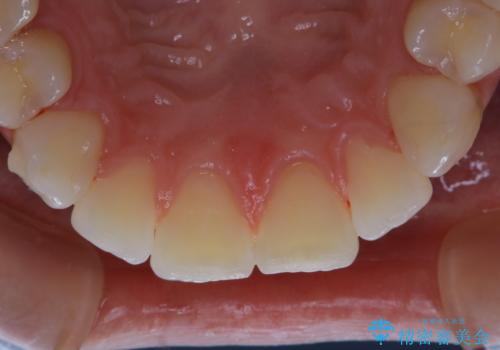

- インビザライン矯正治療中にステインが気になるとのことで来院されました。全体的にステインが付着していたため自費クリーニングPMTC(60分コース)を行いました。

インビザライン矯正治療中は、ご自身の歯にアタッチメントという突起物(効率的に歯の移動を行うため)をつけます。そのため、通常時よりもステインが付きやすい状態になることがあります。

インビザラインは透明なマウスピースなので、ご自身の歯にステインなどが付着していると、見た目に影響してしまうことがあります。

矯正治療中の虫歯・歯周病・口臭予防としても、定期的にPMTCを行うことが大切です。